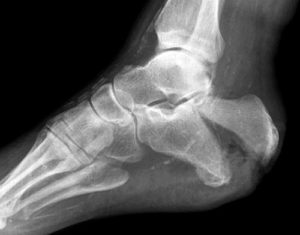

Рентген пяточной кости является самым доступным, информативным и относительно безопасным способом исследования костных и мягких тканей стопы. Такое исследование часто применяется в травматологии, хирургии, ортопедии и помогает выявлять как механические повреждения пятки, так и различные врождённые или приобретённые патологии в этой области.

Из всех костей стопы пяточная имеет наибольший размер. При ходьбе, беге, прыжках на неё приходится большая нагрузка, с чем и связан повышенный травматизм. Рентгеновское исследование позволяет понять, насколько серьёзной является травма пятки, увидеть, есть ли перелом и какого он вида (со смещением или без).

С помощью рентгена в первую очередь оценивается целостность пяточной кости. Затем анализируют её форму и расположение по отношению к другим костям стопы. При выявлении переломов пятки изучается их локализация и направленность. Если перелом оскольчатый, важно оценить, как расположены осколки, нет ли смещения.

Сразу после съёмки снимки проявляются, рентгенолог приступает к расшифровке. Рентгенограмма позволяет выяснить причину боли, определить характер патологического процесса. Для точной интерпретации результата врач может сравнивать снимки здоровой и больной пяток.